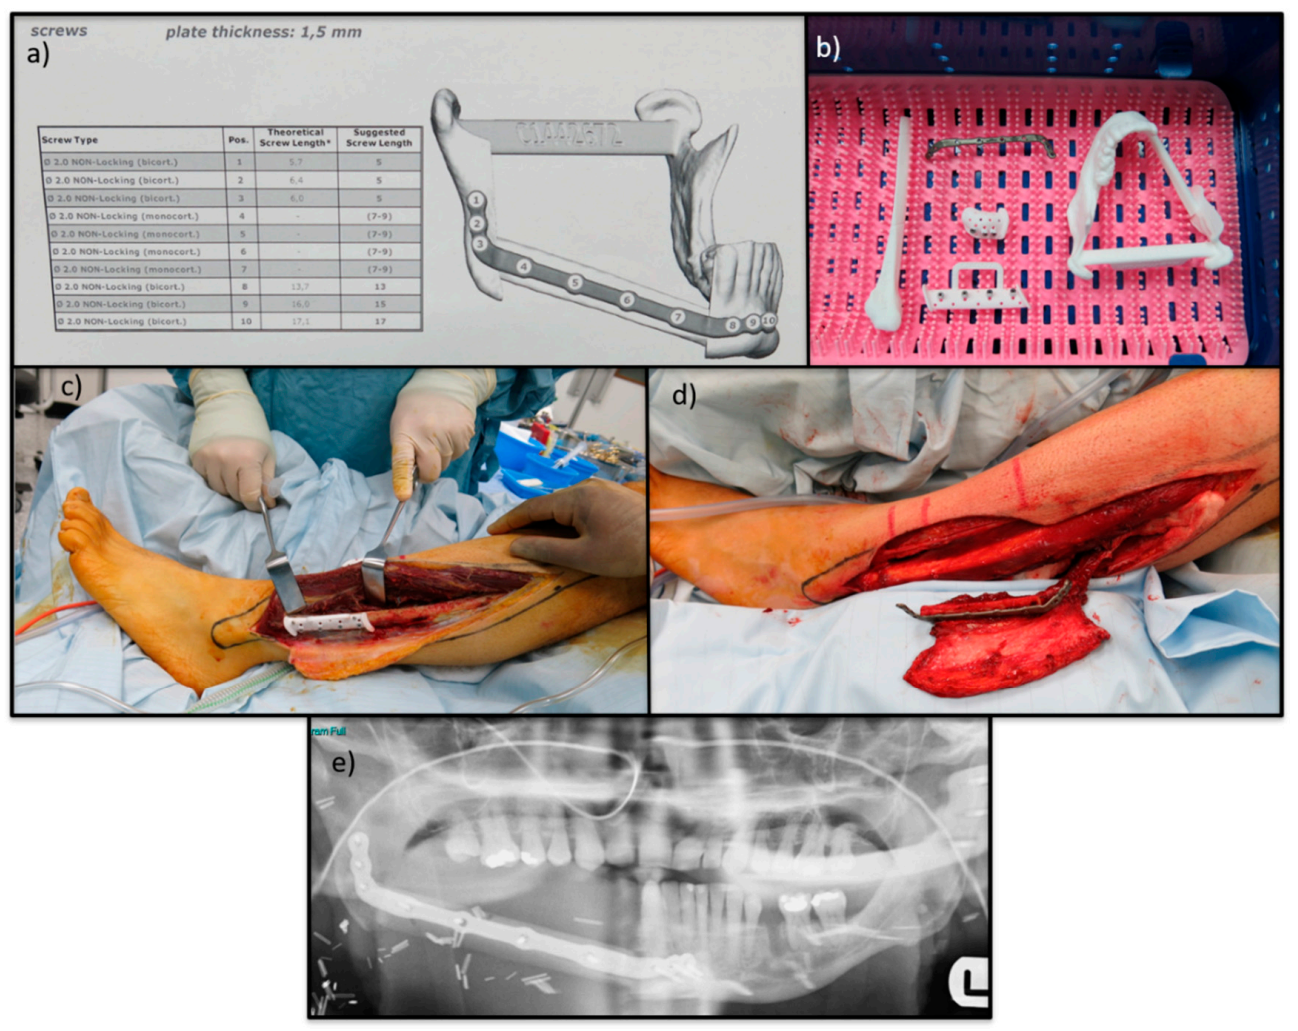

Reconstruction of the mandible and maxilla following wide resection is best performed with vascularised bone [165]. Microsurgical reconstruction of these defects with free osseo-cutaneous/osseo-muscular flaps is the accepted gold standard [166]. The most recent surgical advance includes 3D planning and printing of resection guides and reconstruction plates which allows for customisation and provides optimum oncological and reconstructive surgery with reduced operating times [167](see Figure 9).

Figure 9. Images show the reconstruction of a mandibular OS. (a) Shows the reconstruction plan including the pre-determined screw lengths and locations. (b) Shows the 3D cutting guides, 3D model and the custom reconstruction plate. (c) Shows custom cutting guide on free fibula osseocutaneous flap. (d) custom reconstruction plate attached to free fibular osseocutaneous flap. (e) Shows the follow up orthopantomogram with free fibula osseocutaneous flap fixed in defect.